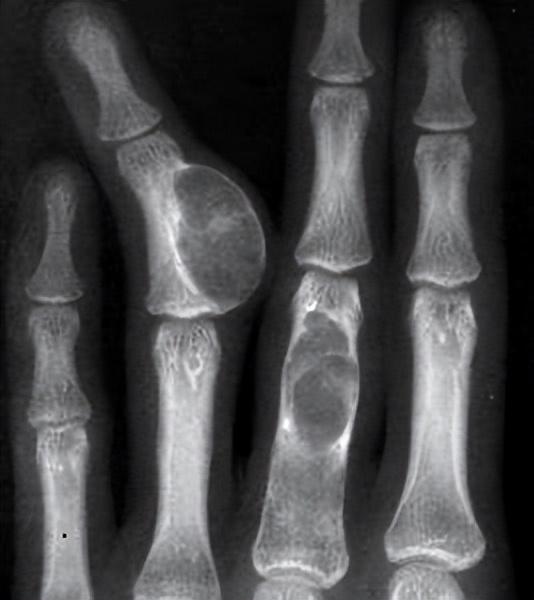

检查结果表明,李明馨腿部的浮肿是骨肉瘤(也就是人们常说的骨癌)引起的,而且李明馨腿部的恶性骨癌已经发展到了晚期,能够治疗好的希望非常渺茫。

医生告诉李明馨的父母,青少年患上骨肉肿瘤很难发现,因为骨肉肿瘤发病初期所导致的身体疼痛跟青少年身体发育所带来的疼痛很接近,往往会被忽视。

随着李明馨腿部骨癌的情况越来越恶化,医生建议李明馨做截肢手术,这样一来,可以防止骨癌细胞的转移扩散,她还可以有一线存活的希望。